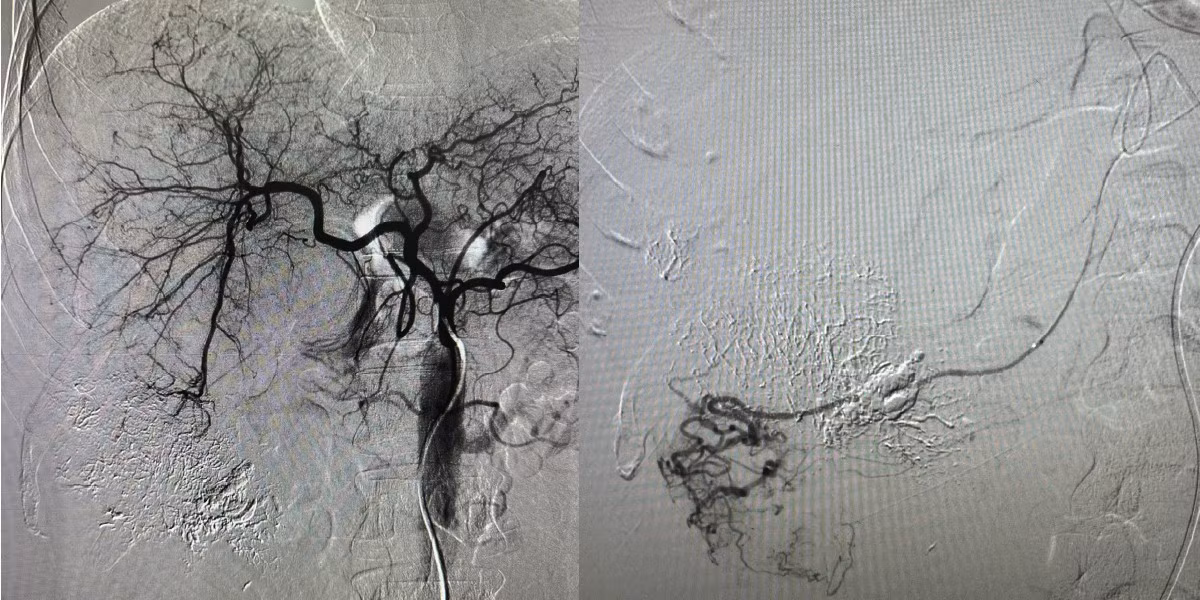

Can thiệp nút mạch gan - Ảnh BVCC

Trong các trường hợp này, phương pháp điều trị hiệu quả được ưu tiên là kỹ thuật chụp và nút mạch gan. Bằng việc sử dụng hệ thống chụp mạch số hóa xóa nền (DSA), các bác sĩ sẽ đưa một ống thông có kích thước rất nhỏ vào hệ thống mạch máu để tiếp cận vị trí đang chảy máu.

Tại đây, chất gây tắc mạch sẽ được bơm vào nhằm làm tắc hoàn toàn mạch máu bị tổn thương, giúp cầm máu nhanh chóng, hạn chế biến chứng và tăng cơ hội sống sót cho người bệnh.